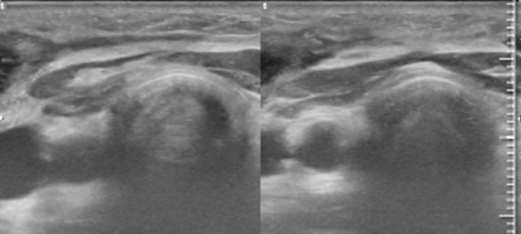

- Siêu âm tuyến giáp (01/07/2022):

+ Thùy phải có cấu trúc giảm âm, bờ đều, ranh giới với tổ chức xung quanh không rõ, kích thước 4x1x1cm (TIRADS 4)

+ Thùy trái có cấu trúc kích thước 4.5x2.5x1cm (TIRADS 3)

+ Hạch cổ phải nhóm 4 có vài hạch, đường kính 4-8mm, hạch lớn nhất kích thước 15x20mm, bên trái có hạch nhỏ đường kính 4mm

- Siêu âm tuyến giáp

Hình 10: Siêu âm tuyến giáp (08/04/2024): Hình ảnh phù nề nhẹ phần mềm dưới da tương ứng vị trí vết mổ